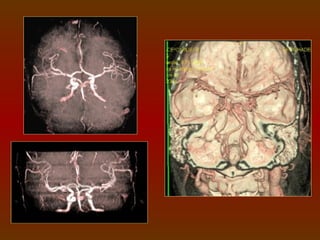

CÍRCULO OU POLÍGONO DE WILLIS

É um círculo de artérias que suprem o cérebro. Foi nomeado em

CIRCULAÇÃO SANGUÍNEA DO CÉREBRO

O sangue chega ao cérebro através das artérias vertebrais e

das artérias carótidas internas, que se comunicam através do

polígono de Willis, este é uma anastomose arterial que fornece o

suprimento sangüíneo para os hemisférios cerebrais, sendo

formado pelas artérias cerebrais anteriores e posteriores, artérias

comunicantes anterior e posteriores e pela carótida interna.

IMPORTÂNCIA FISIOLÓGICA

O arranjo das artérias no

Polígono   de    Willis    cria uma

redundância na circulação cerebral.

Se uma parte do círculo estiver

bloqueada ou estreitada (estenose),

ou se uma das artérias que suprem o

polígono    está     estreitada  ou

bloqueada, o fluxo sanguíneo dos

outros vasos sanguíneos podem

muitas vezes preservar a perfusão

cerebral .

ESTUDO DO POLÍGONO DE WILLIS

 1 mm espessa X 1 mm incremento.

 Em média 100 ml de contraste, a 3ml/s.

A marcação vai da

base do seio

esfenoidal ao topo

do corpo caloso.